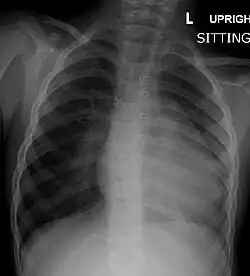

A chest X-ray of a child with tetralogy of Fallot

Chest radiograph

Before more sophisticated techniques became available, chest X-ray was the definitive method of diagnosis. The abnormal "coeur-en-sabot" (boot-like) appearance of a heart with tetralogy of Fallot is classically visible via chest X-ray, although most infants with tetralogy may not show this finding.[50] The boot like shape is due to the right ventricular hypertrophy present in TOF. Lung fields are often dark (absence of interstitial lung markings) due to decreased pulmonary blood flow.[51]: 171–172